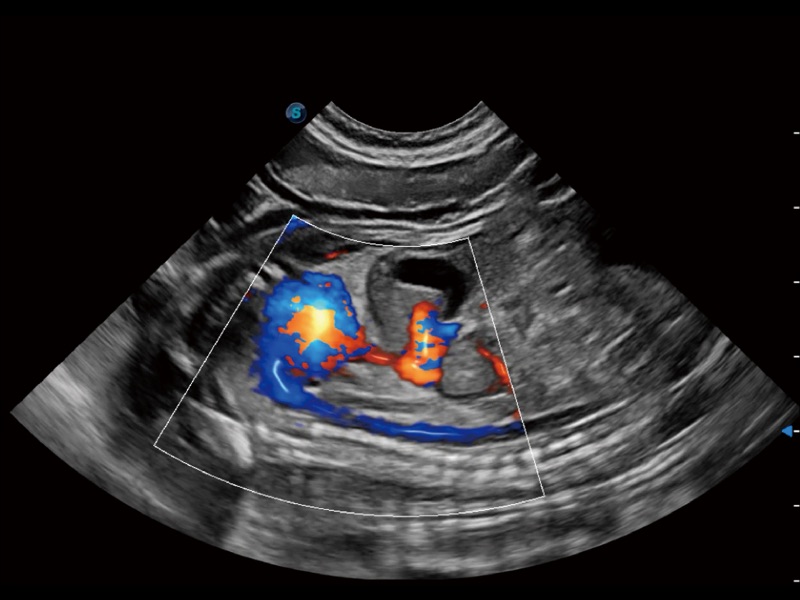

通过创新的 Matrix E自适应滤波器和超长时间域算法,极大提升超低速微细血流的检出能力,同时更精准地滤除软组织和噪声信号,为兽用医生提供以往无法通过常规血流获得的疾病诊断信息。

通过色彩血流和实时宽景相结合,可观察到完整的静脉或动脉的血流,方便医生检查。实时扫查过程中,如有任何操作失误也可以很容易地进行回扫擦除,而不会中断扫查。